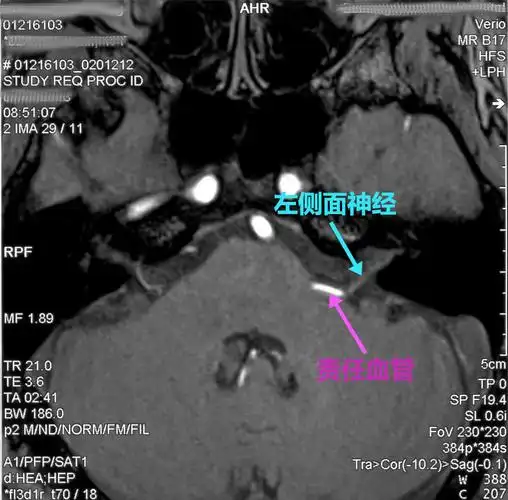

该病典型的 mri 表现为双侧面神经发育不全,在平衡稳态梯度回波序列

磁共振检查如3d-tof-mra,fiesta等,有助于明确责任血管和面神经之间的